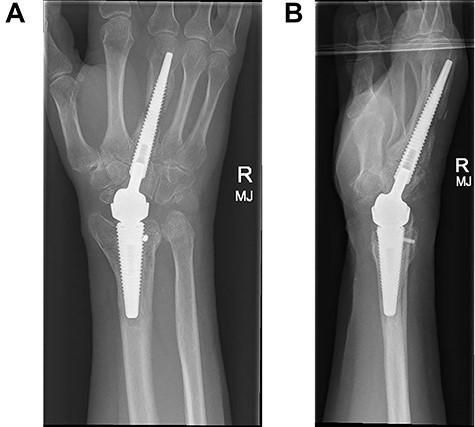

Following appropriate consultation and consent, she underwent total wrist arthroplasty. She reported complete pain relief and an improved range of movement. Ten weeks following surgery the patient presented in the emergency department following a fall. She landed heavily on the dorsiflexed hand and wrist, immediately noticing a change. Imaging confirmed that she had sustained a periprosthetic fracture in the middle finger metacarpal with dorsal displacement of the implant (Fig. 2A and B). Following a trial of non-operative treatment, she underwent revision surgery. The distal metacarpal implant was removed and replaced with a longer implant and the metacarpal fracture defect region was reinforced with autologous bone graft (Fig. 3A and B).

(A and B) PA and lateral radiographs following revision surgery to a longer metacarpal implant.

Three months following surgical treatment of her periprosthetic fracture, when reviewed in the outpatient clinic, the fracture had united and she demonstrated an excellent range of pain free motion and improved wrist function reflected in an improved PRWHE score from 66 preoperatively to 22, 3 months after surgery.